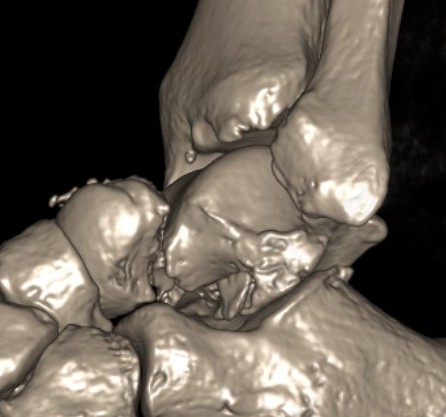

Anatomical reduction + fixation

1. Remove loose bodies from subtalar joint

2. Reduction - avoid varus and shortening medial neck

- often medial comminution

Canale view

- evaluates talar neck

- foot everted 15 deg

- look for medial shortening / varus